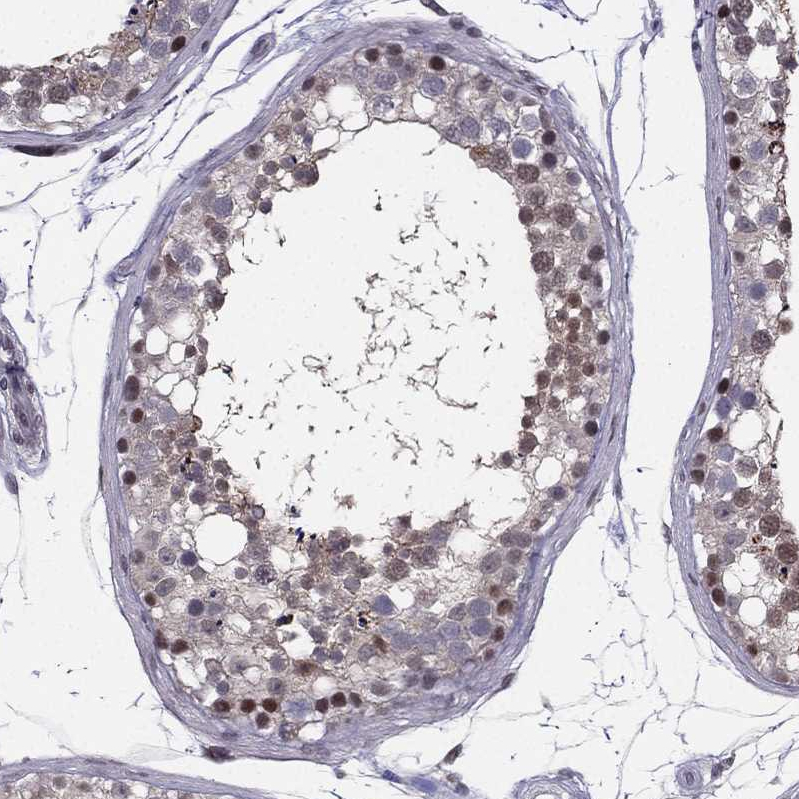

Immunohistochemical staining of human skeletal muscle shows moderate nuclear positivity in myocytes.